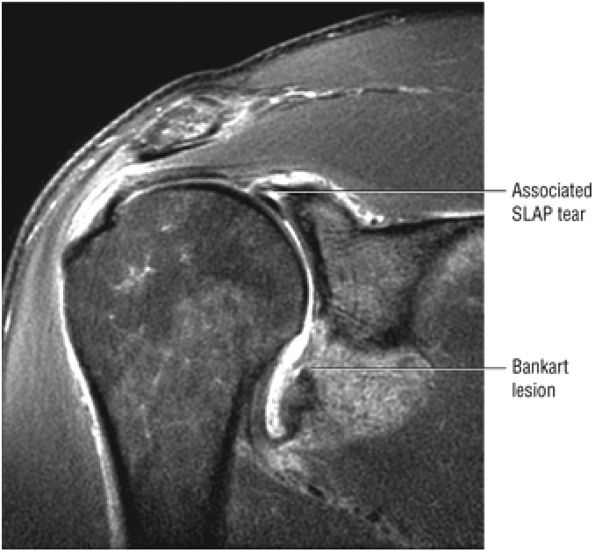

FIGURE 8.152 ● (A) Posterosuperior view color graphic showing a massive rotator cuff tear involving the supraspinatus, infraspinatus, and subscapularis tendons. (B) Coronal FS PD FSE image showing the wave sign of a retracted supraspinatus tendon as a sign of a reparable acute cuff tear without associated scarring.

|

![]() |